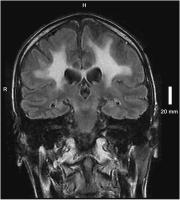

Abbildung 3: Sagittale T1 des Gehirns mit Kontrastmittel: zarte, randständige Kontrastmittelaufnahme

Keywords:

Adrenomyeloneuropathie

,

Gehirn

Kontrastmittel

MRT

Neurologie